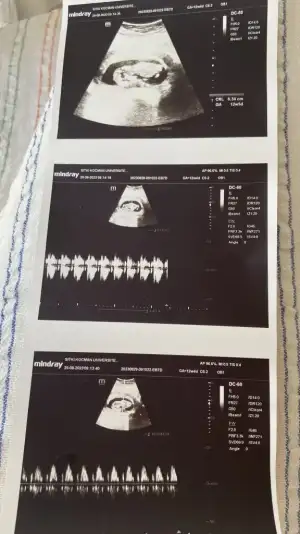

Bu da benim 12+4 ultrason görüntüsüFotoğraf atabilir misin peki merak ettimm, yapılı duruyor derken nasıl yaniay siz kız dedikçe bence erkek olcak gibi ben söyleyeyim size sanki

Eklentiler